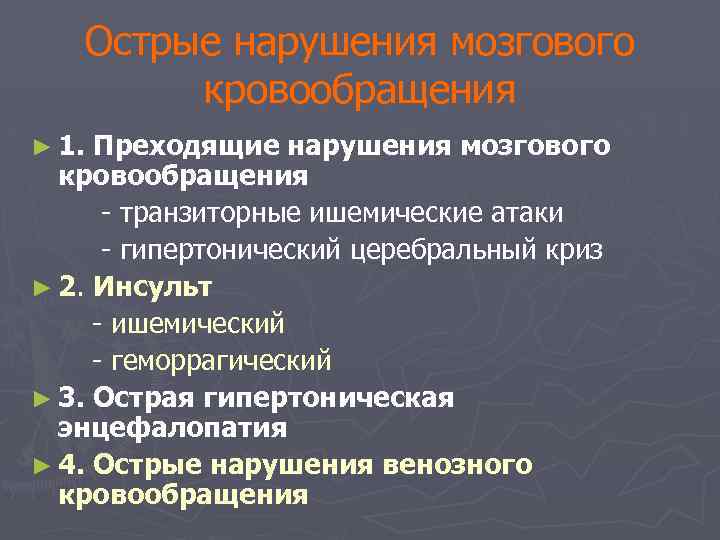

Острые нарушения мозгового кровообращения ► 1. Преходящие нарушения мозгового кровообращения - транзиторные ишемические атаки - гипертонический церебральный криз ► 2. Инсульт - ишемический - геморрагический ► 3. Острая гипертоническая энцефалопатия ► 4. Острые нарушения венозного кровообращения